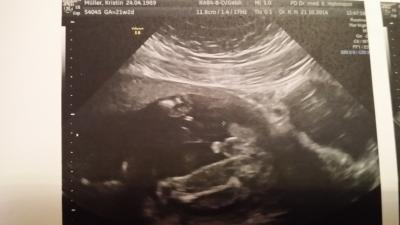

Soooo heute ist wohl der beste Tag seit langem für mich . Ich hab das Ergebnis der Fruchtwasserpunktion und alles ist bestens Zwar wurde ja nochmal festgestellt, dass es ein junge wird, aber ich musste heute zum organscreening und was soll ich sagen- sein bestes stück war nicht zu übersehen Ansonsten auch alles top. War sehr kooperativ beim US, sodass der arzt wirklich alles sehen konnte was nötig ist. Und 428 g wiegt der kleine schon Versuche mal das Beweisbild anzuhängen- mal sehen ob es klappt

Bild zu Ergebnis Fruchtwasserpunktion - Forum für März - Mamis

Das ist ja mehr als eindeutig :) freut mich dass alles ok ist